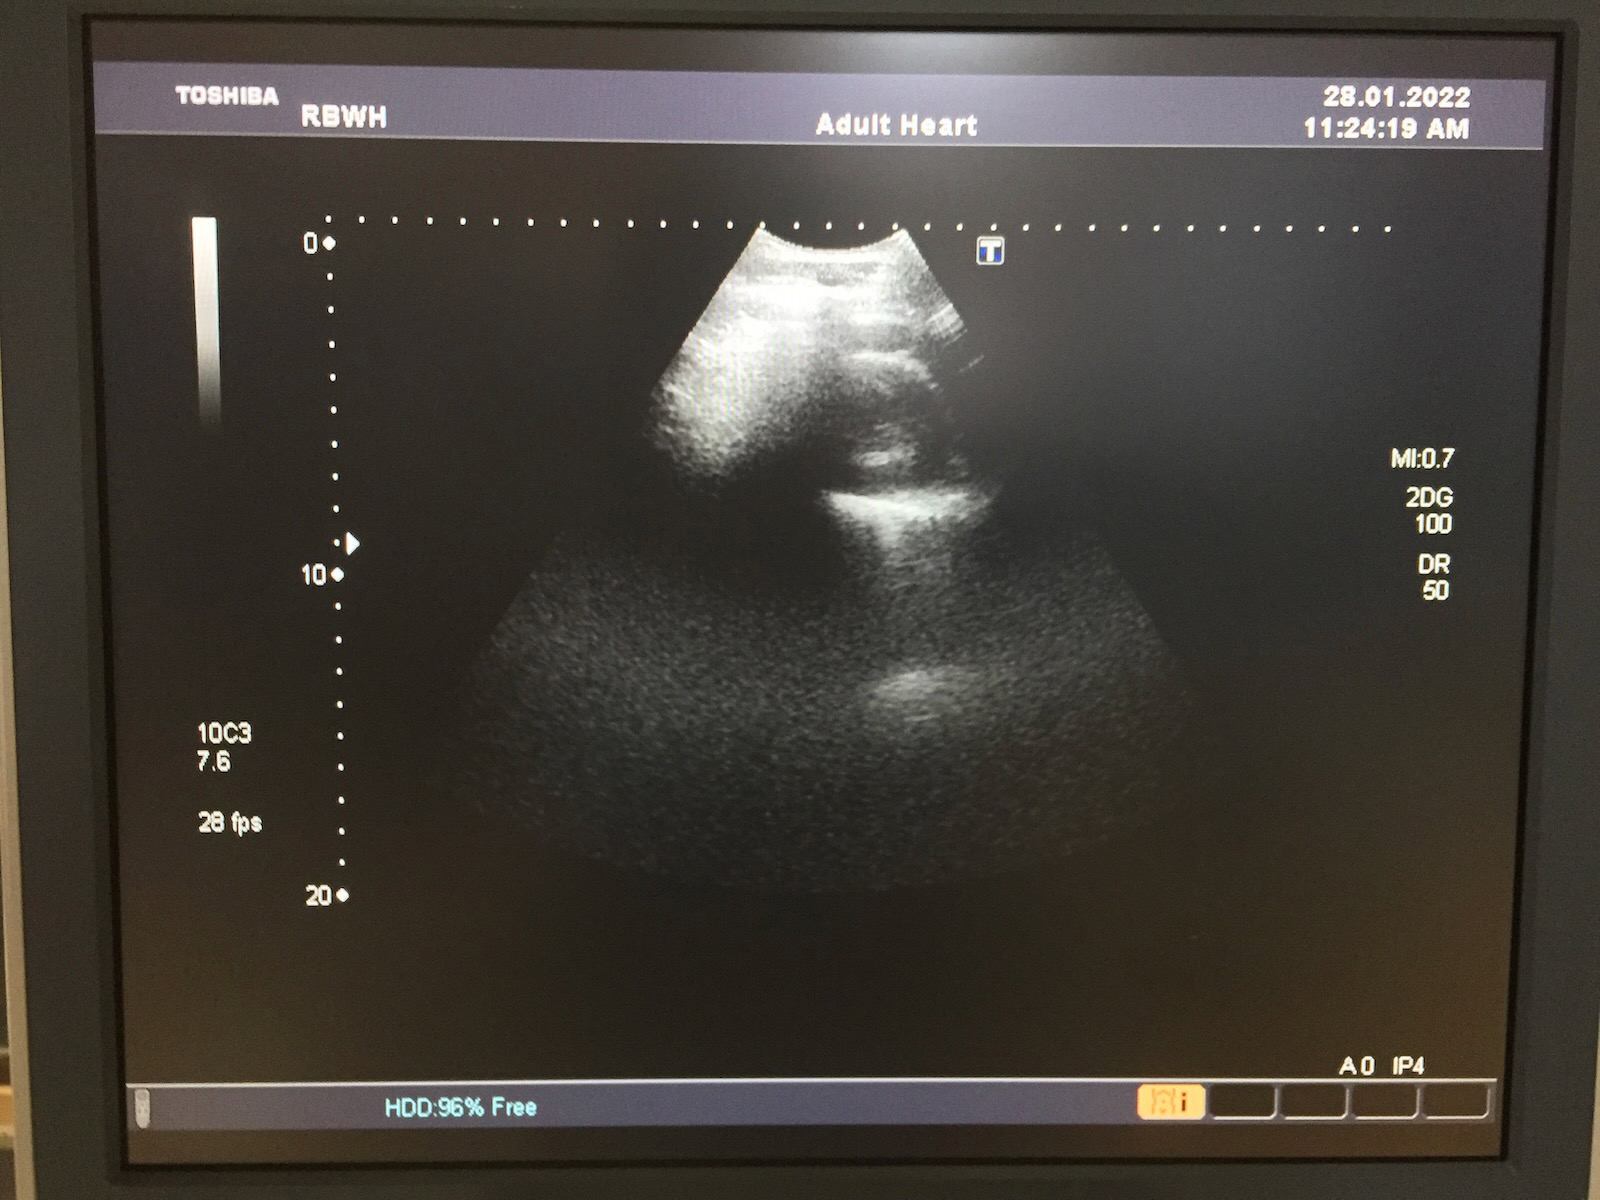

Probe has been tested on a Toshiba Aplio XG SSA-790A Ultrasound Machine and working well